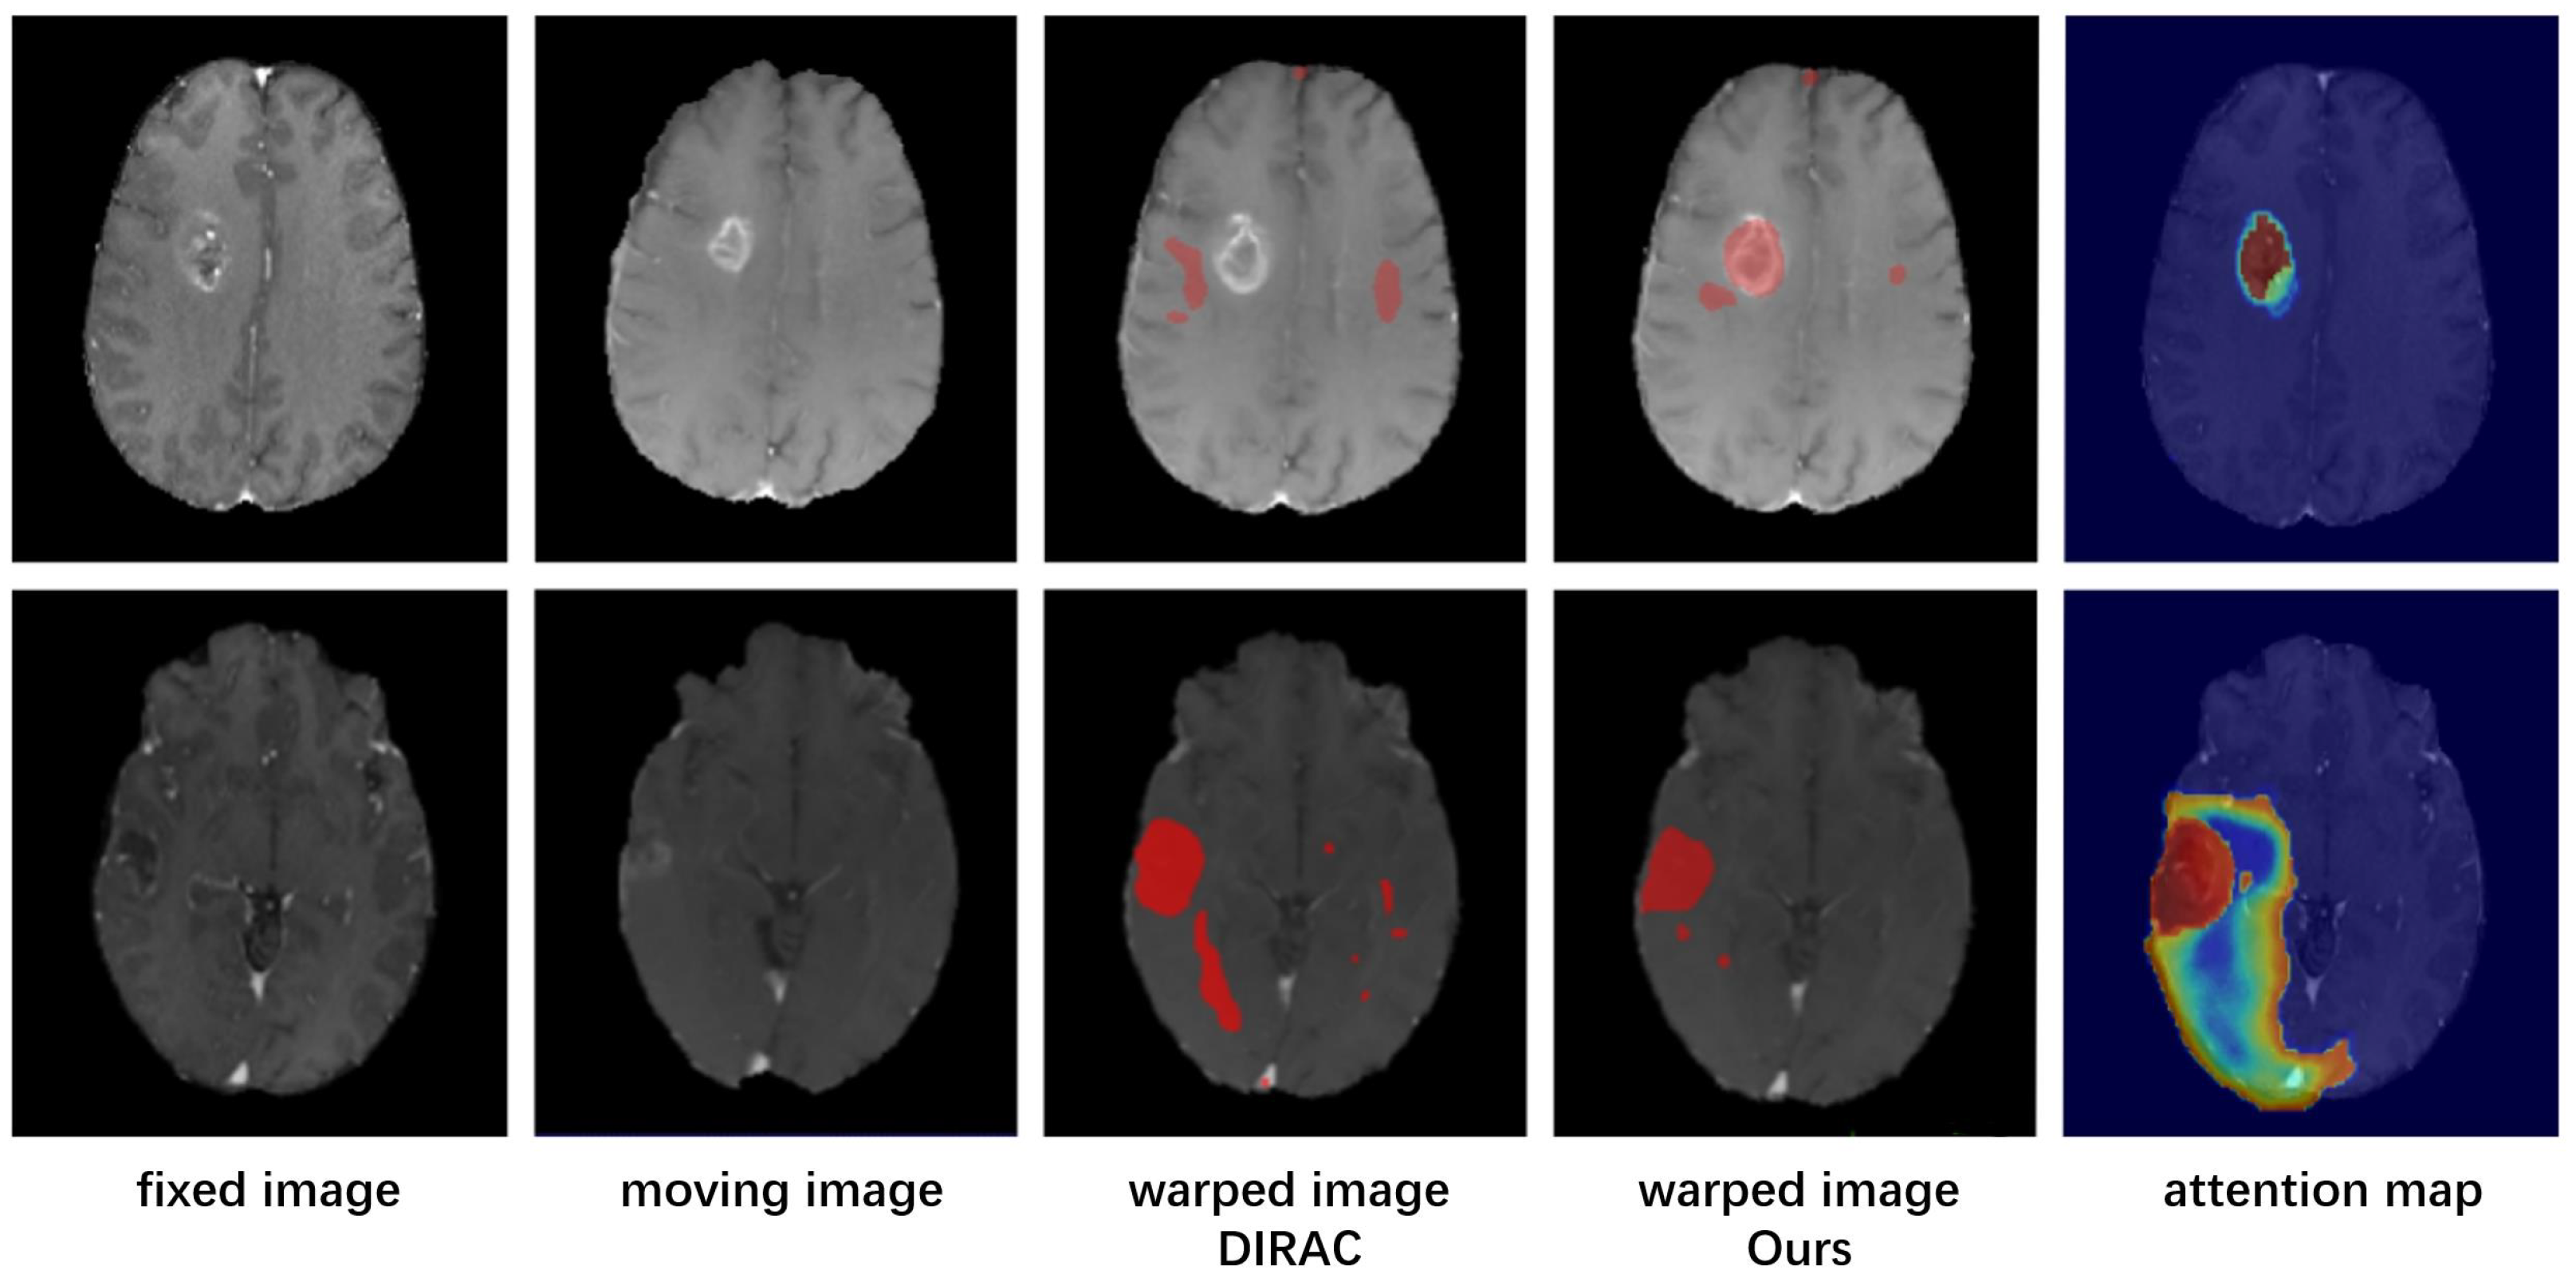

- To further eliminate adverse effects of possible registration biases, our model incorporates a corrected attention module that enhances the model’s focus on areas with significant deformation and integrates the clinical data of the area if that certain pathological area of the preoperative image should have no corresponding relationship.

2.4. Corrected Attention Module